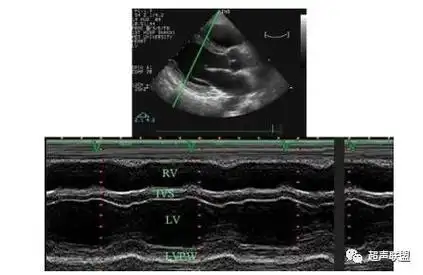

纯干货心脏超声经验分享